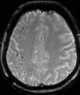

Cerebral neoplasm

Cerebral edema is excess accumulation of fluid (edema) in the intracellular or extracellular spaces of the brain. This typically causes impaired nerve function, increased pressure within the skull, and can eventually lead to direct compression of brain tissue and blood vessels. [Source: Wikipedia ]